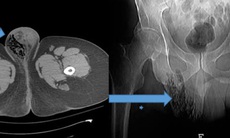

ThS.BS Lê Xuân Triệu – chuyên khoa Ung thư cho biết, hình ảnh CT cho thấy vị trí thủng nghi ngờ xuất phát từ đại tràng, rõ nhất ở đoạn sigma. Bệnh nhân được chỉ định phẫu thuật cấp cứu ngay lập tức, đồng thời làm hậu môn nhân tạo nhằm kiểm soát nhiễm trùng trong ổ bụng.

Trong quá trình phẫu thuật, ê-kíp tiến hành lấy mẫu mô để sinh thiết. Kết quả sau đó xác định bệnh nhân mắc ung thư đại tràng, khối u vỡ gây viêm phúc mạc toàn thể. Theo bác sĩ Triệu, đây là biến chứng nặng, có thể diễn tiến nhanh nếu không được can thiệp kịp thời.